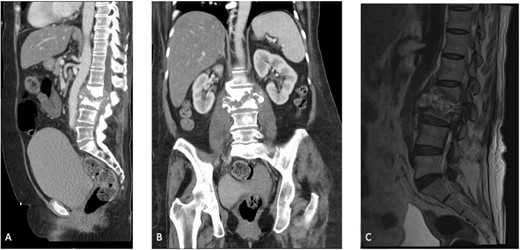

Initial laboratory results showed a normal white blood cell count of 9.3 × 103/μL, elevated erythrocyte sedimentation rate of 47 mm/h, and high-sensitivity C-reactive protein of 8.26 mg/dL. Preoperative computed tomography (CT) and magnetic resonance imaging (MRI) of the patient’s abdomen and pelvis demonstrated L2–L3 discitis-osteomyelitis with a large anterior epidural abscess (Fig. 1A–C).

(A) Sagittal section of a CT scan depicting L2–L3 discitis-osteomyelitis. (B) Coronal section of a CT scan depicting L2–L3 discitis-osteomyelitis. (C) Sagittal MRI of the lumbar spine demonstrating severe L2–L3 discitis and L2–L3 osteomyelitis with a large anterior epidural abscess causing severe spinal stenosis at the L2 and L3 levels.